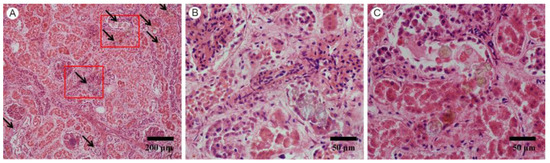

3.1. Pathological Findings